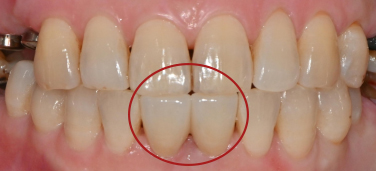

보라매역 치과 에서 구강 내를 확인해보니

아래 앞니사이의 공간이 있으셨고

치아와 잇몸경계부위의 착색과 치석이 있었습니다.

앞니 사이의 공간이 있었던 환자 분이었는데요.

신경치료를 하면서 크라운 치료로

앞니 사이의 공간을 줄여드리고

심미적으로 더 나은 치아의 형태를

만들어 드리는 것이 필요 해 보입니다.

환자 분도 색깔이나 모양에 만족하시며

치료를 마무리 지었고 앞으로 정기검진을 통하여